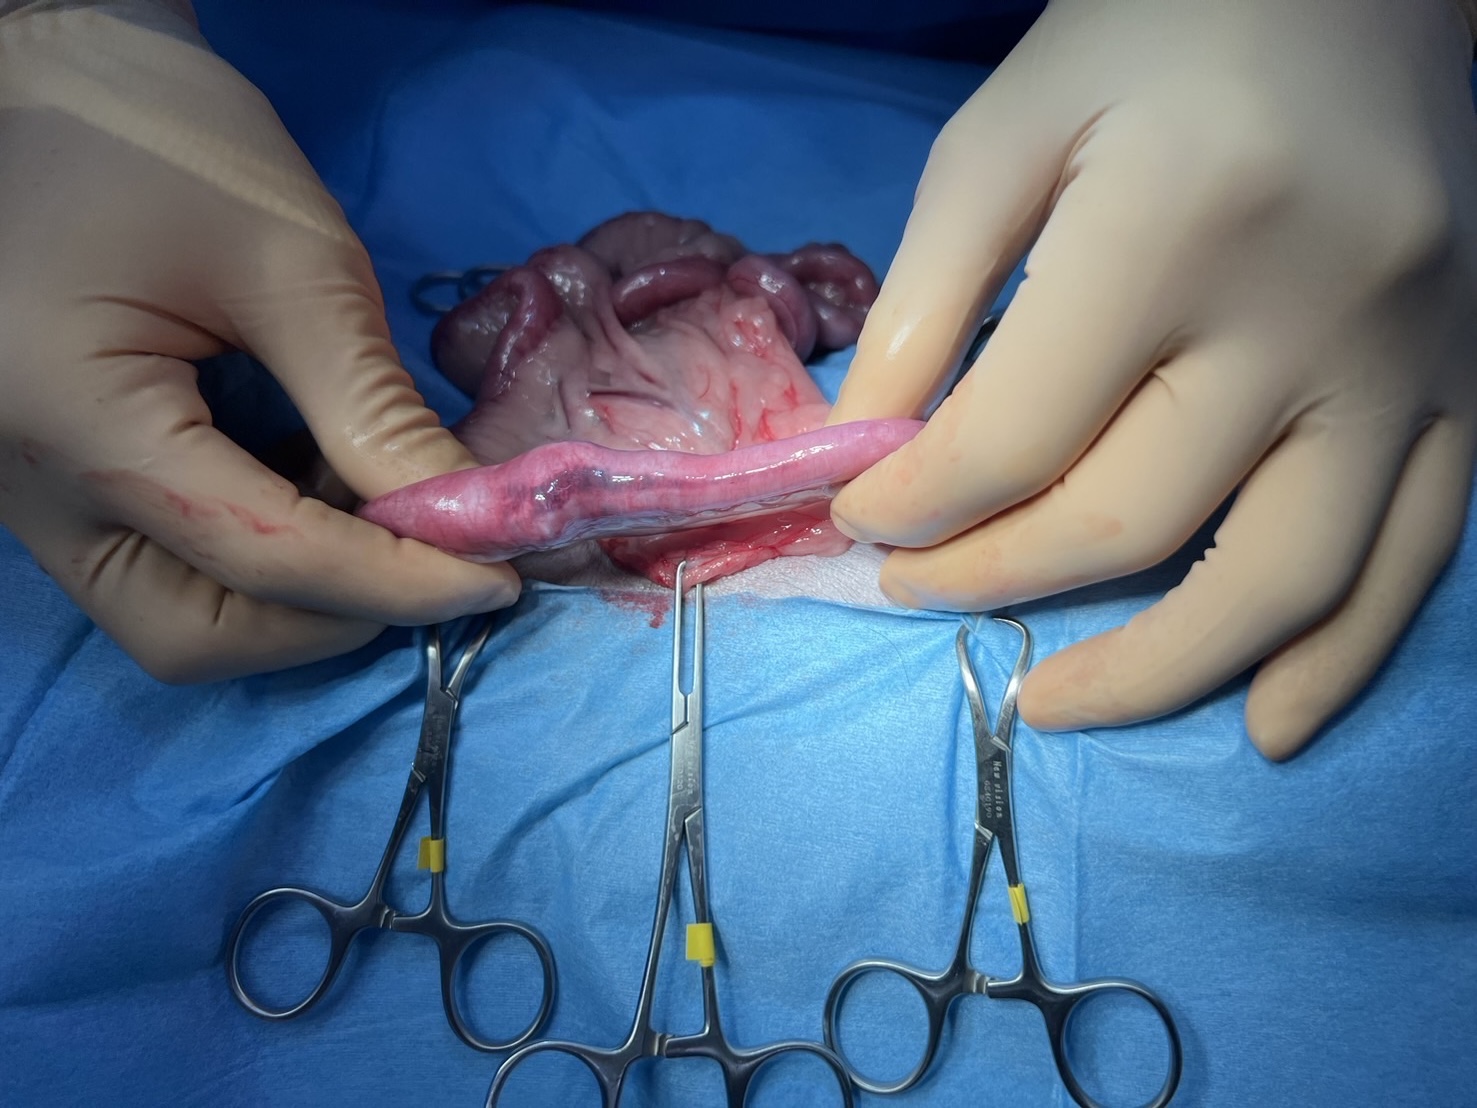

【手術画像】

空腸領域に閉塞物を見つけ、直上をメスで切開し異物の摘出を実施いたしました。

摘出された異物は毛糸やフェルトなどで構成されているようなもので、やや硬く、腸管を完全に閉塞させる大きなものでした。